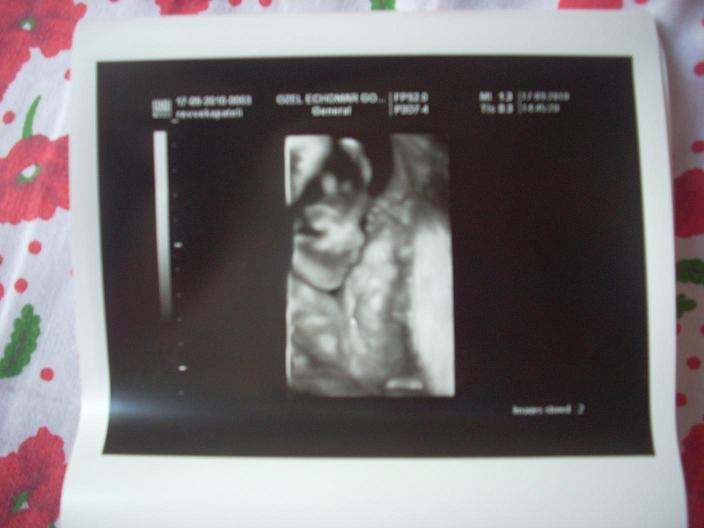

Ρεββεκακι ολοκληρη κοπελα εγινε η Λυδια!! ;) Σχεδον μισο κιλο!!! :o Τελεια!!!!